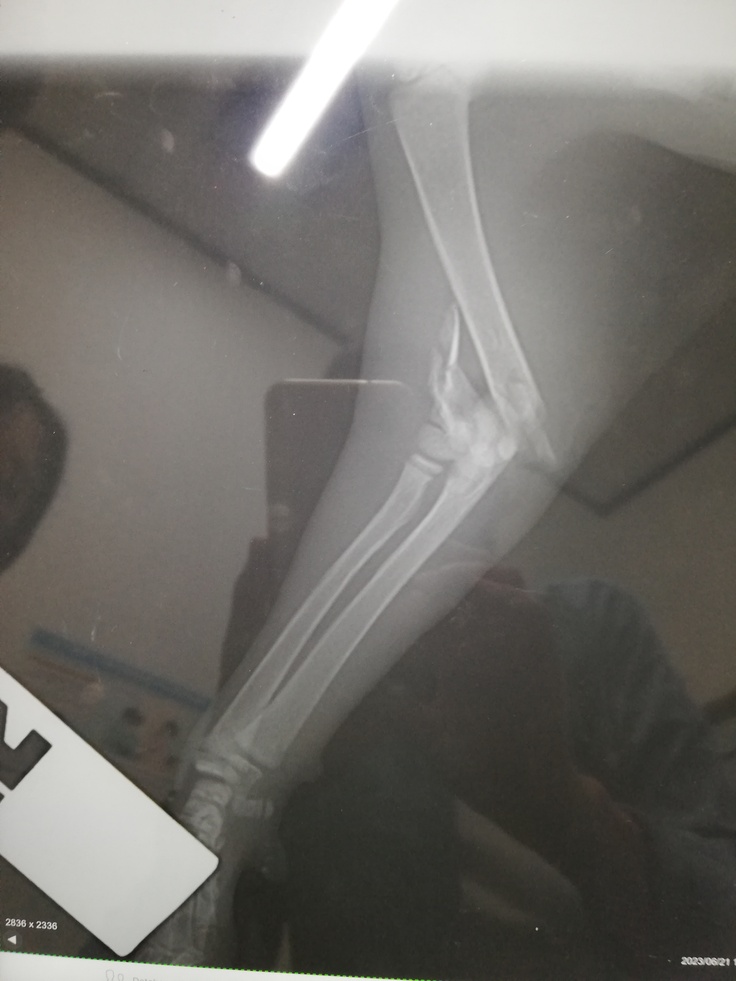

今年6月21日犬の散歩中に、草むらから尋常じゃない鳴き声するので行ってみると、右脇から大量な血と骨が出ている子猫を発見しました。

急いで動物病院へ連れていき、レントゲンの結果は開放骨折と診断され切断手術になりますと言われました。

2023年06月21日 初診料 17782円